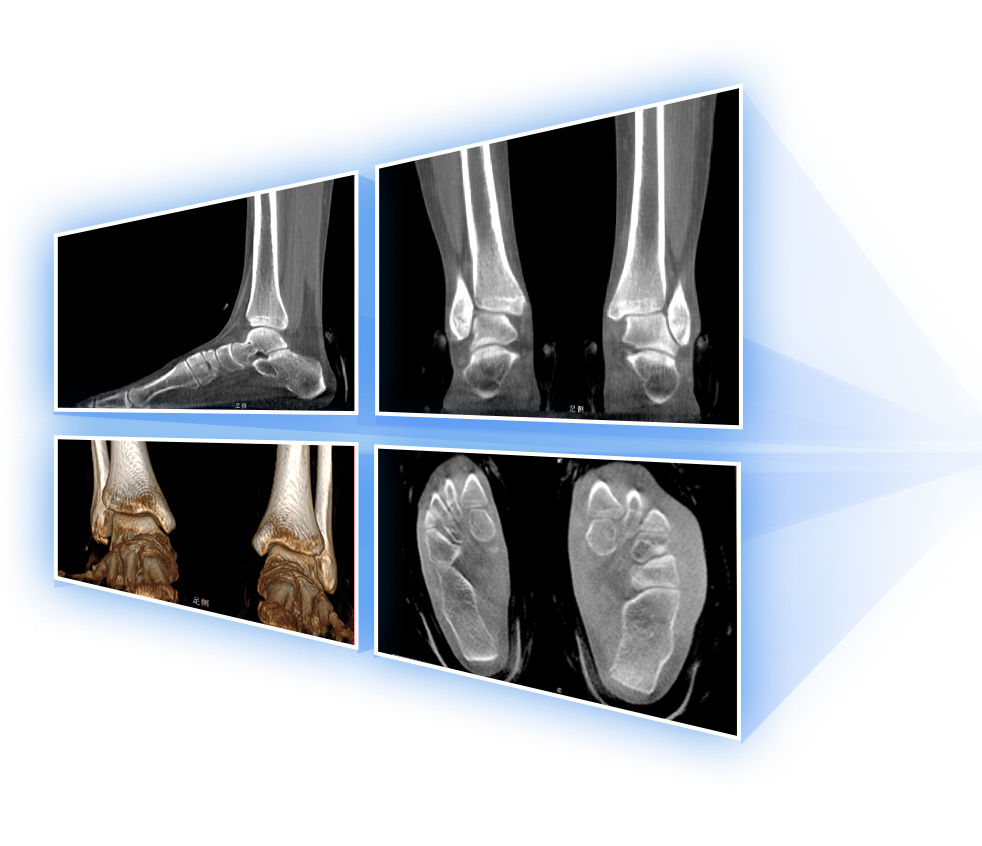

足踝

精准诊断

手术方案规划

术后随访

VR体绘制重建